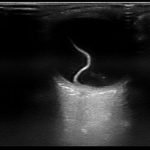

Bedside ocular ultrasound revealed a serpentine, hyperechoic membrane that appeared tethered to the optic disc posteriorly with hyperechoic material underneath. These findings are consistent with retinal detachment (RD) and associated retinal hemorrhage.

Findings on bedside ultrasound consistent with RD include a hyperechoic membrane floating in the posterior chamber. RD usuallyremain tethered to the optic disc posteriorly and do not cross midline, a feature distinguishing them from posterior vitreous detachments. Associated retinal hemorrhage, seen as hyperechoic material under the retinal flap, can often be seen.1,2 US can also distinguish between “mac-on” and “mac-off” detachments. If the retina is still attached to the macula (mac-on), central vision is preserved and emergent repair is essential before progression to a mac-off RD.2 In a prospective observational study, emergency physicians achieved 97% sensitivity, and 92% specificity in diagnosing this pathology on bedside US. Optic disc edema and vitreous hemorrhage accounted for the false positives.2 Emergent ophthalmology consultation was obtained for our patient who saw the patient the same day for vitrectomy.